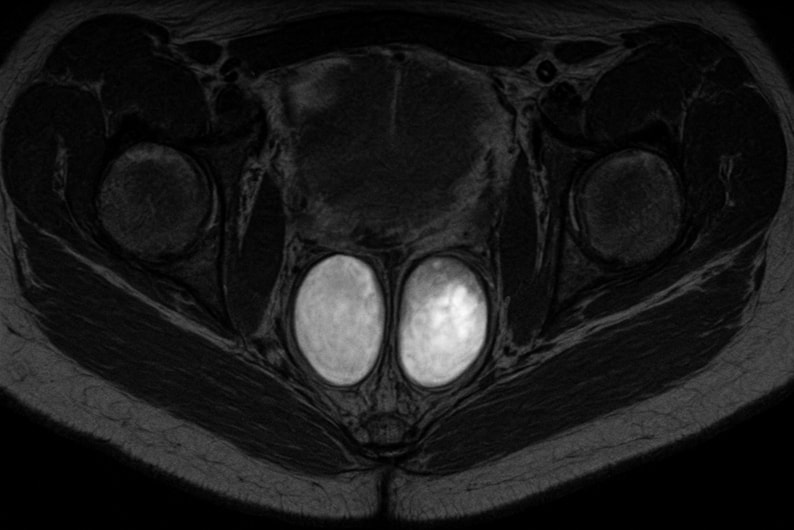

Магнитно-резонансная томография мошонки с контрастом — один из самых информативных методов визуализации, применяемых в современной андрологии и урологии. Исследование основано на безопасном воздействии магнитного поля, которое создает послойные снимки тканей с высокой детализацией. Благодаря этому врачи видят мельчайшие структуры и могут оценить полость мошонки, состояние яичек, придатков и сосудов.

МРТ мошонки с контрастом особенно ценна при диагностике воспалений, кист, гематом и при подозрении на опухоль яичка. После введения контраста повышается четкость изображения, улучшается визуализация мягких тканей, что помогает точно определить границы новообразований и составить представление о структуре опухоли. Это дает возможность поставить точный диагноз даже в сложных случаях, когда другие методы диагностики не дают ясной картины.

После этого начинается основное сканирование. Процедура проводится под контролем медперсонала, полностью безболезненна и занимает около 25–30 минут. Благодаря использованию контрастного препарата, врач получает изображения с максимальной четкостью, где хорошо видны сосуды, ткани и мелкие образования.

Современные аппараты обеспечивают высокое разрешение, позволяя изучать структуру опухоли и строение тканей в разных плоскостях. В клинике используется оборудование последнего поколения, обеспечивающее точную диагностику без вредного излучения.

После завершения исследования врач анализирует изображения на специальной рабочей станции. С помощью контраста можно оценить не только анатомию органов, но и особенности кровоснабжения, плотность тканей и наличие очаговых изменений.

МРТ мошонки с контрастным веществом помогает отличить доброкачественные образования от злокачественных, определить степень распространения процесса и подобрать дальнейшую тактику лечения. Врач оценивает структуру опухоли, состояние сосудов, наличие воспалений и посттравматических изменений.